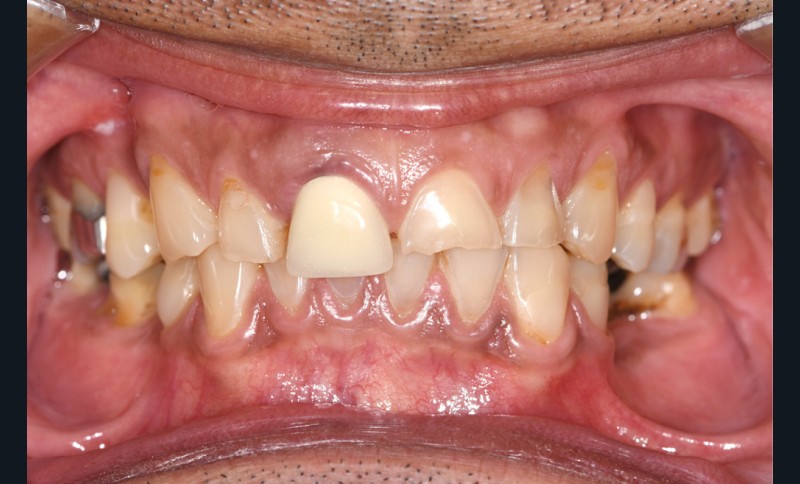

L’étiologie de cette usure est multifactorielle, revêtant une composante de type attrition (usure par contact dento-

dentaire), une composante abrasive avec un brossage traumatique et, en dernier lieu, une légère composante tribo-érosive de par une pratique importante de sport avec gel et boisson acide (fig. 1-4) [1].